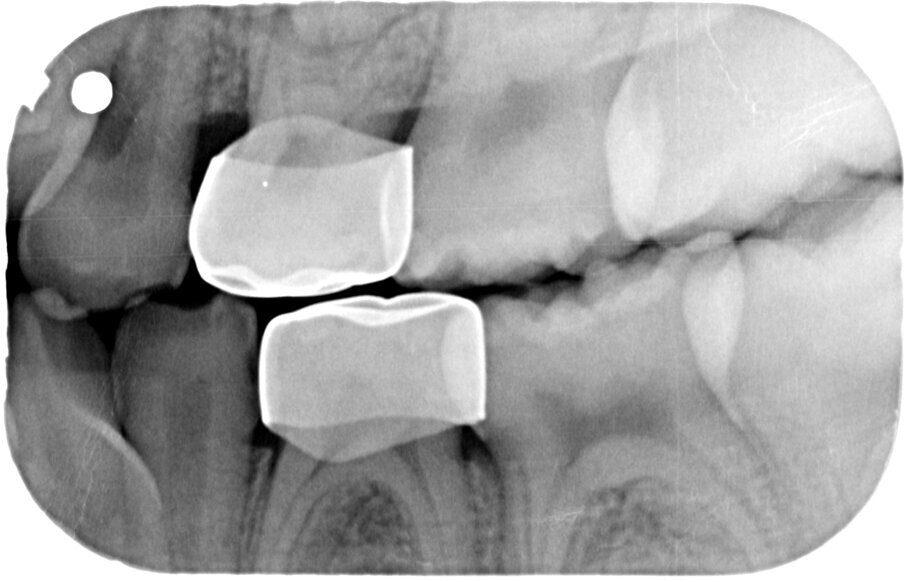

Afbeelding 11a-b. Casus 3: 23-01-20. In november met Hall-techniek geplaatste kroon met ‘50%-prognose’ om enerzijds pijn en anderzijds narcose te voorkomen.

Groot voordeel van de Hall-techniek is dat deze eigenlijk altijd eenmalig is. De kans op herbehandeling vanwege loslaten, breuk, secundaire cariës of wat dan ook is lager dan bij elke andere therapie. De diepte of de grootte van de caviteit is van secundair belang. De prognose van de therapie wordt bepaald door de afwezigheid van pulpa-pathologie en door de aanwezigheid van een op een bitewing zichtbare laag van gezond dentine, ‘a clear band of dentine’, tussen de caviteit en de pulpa (afbeelding 12-13).